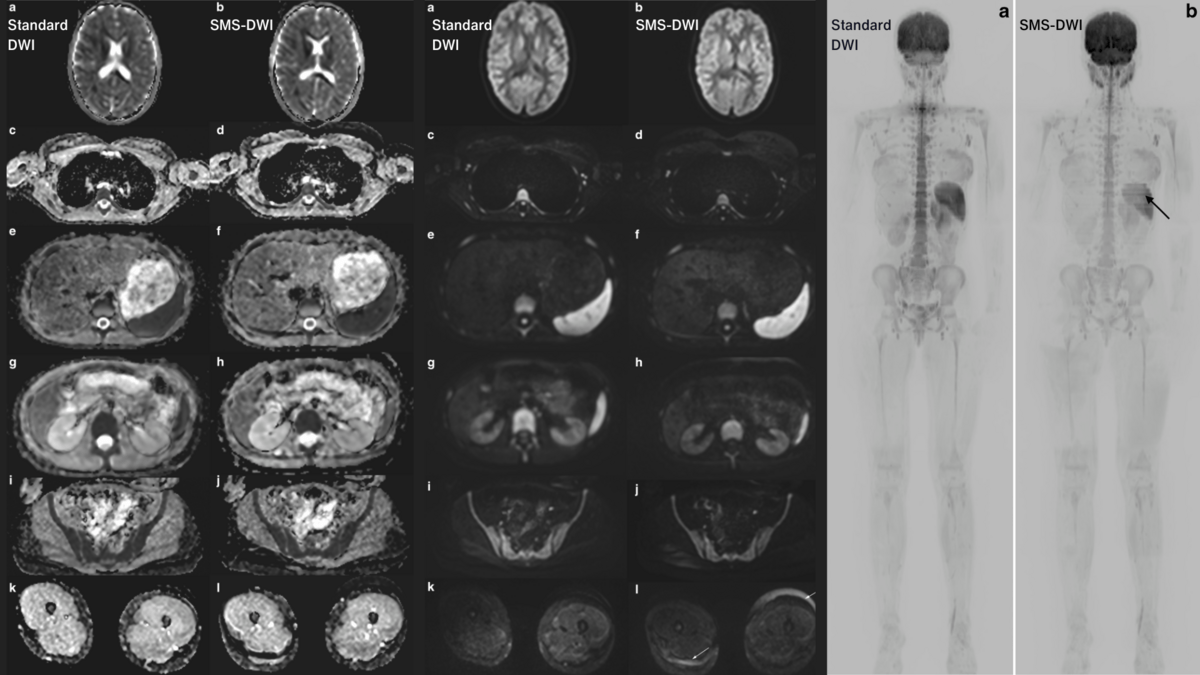

Highresolution wholebrain dynamic contrastenhanced MRI using

New Technique Speeds Up WholeBody MRI for Children Without Sacrificing How To Improve Image Quality In Mri In this chapter, we review both practical and advanced techniques to achieve high image. High transmitter bandwidth is the most appropriate option to select when scanning areas with metal implants. This option will significantly reduce. In mri, snr is primarily used for image evaluation and contrast enhancement measurement. After reading this chapter, you should be able to: Additionally, snr is. How To Improve Image Quality In Mri.

Highresolution wholebrain dynamic contrastenhanced MRI using How To Improve Image Quality In Mri This option will significantly reduce. In this chapter, we review both practical and advanced techniques to achieve high image. To get a useful picture, the amount of signal from. Several strategies can be used to improve image quality in mri scans. After reading this chapter, you should be able to: In mri, snr is primarily used for image evaluation and. How To Improve Image Quality In Mri.